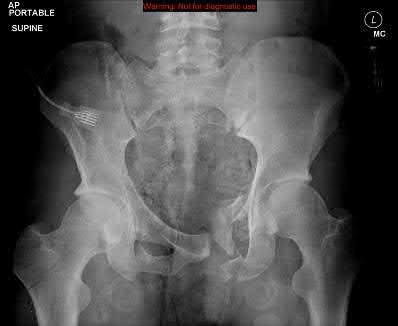

A 23-year-old female is an unrestrained driver in a motor vehicle collision, sustaining the injury shown in Figure A. She subsequently undergoes reduction and percutaneous bilateral iliosacral screw placement. Which of the following is the most likely neurologic complication associated with percutaneous iliosacral screw insertion?

Figure A shows an unstable bilateral pelvic ring injury. Percutaneous posterior iliosacral screw fixation places the L5 nerve root at risk as it courses across the sacral ala. Injury to the L5 nerve root would typically result in weakness in great toe extension and sensory changes on the dorsum of the foot. It is important to notice that L5 often partially innervates tibialis anterior along with L4, so weakness to ankle dorsiflexion may be present as well. Illustration A shows the post-operative films with bilateral iliosacral screws.

Routt et al examined the sacral slope and sacral alar anatomy in cadavers and a series of consecutive patients. They determined that the pelvic outlet and lateral sacral plain films provide the best plain radiographic views of the sacral ala. They recommended routine usage of these views intraoperatively to guide screw placement.

In another study, Routt et al reported on the early complications of percutaneous placement of iliosacral screws for treatment of posterior pelvic ring disruptions. While technically challenging, this technique leads to less blood loss and lower rates of infection compared to traditional open techniques.

Illustration B displays the root diagrams for sensation, reflex, and motor of the L4-S1 nerves.